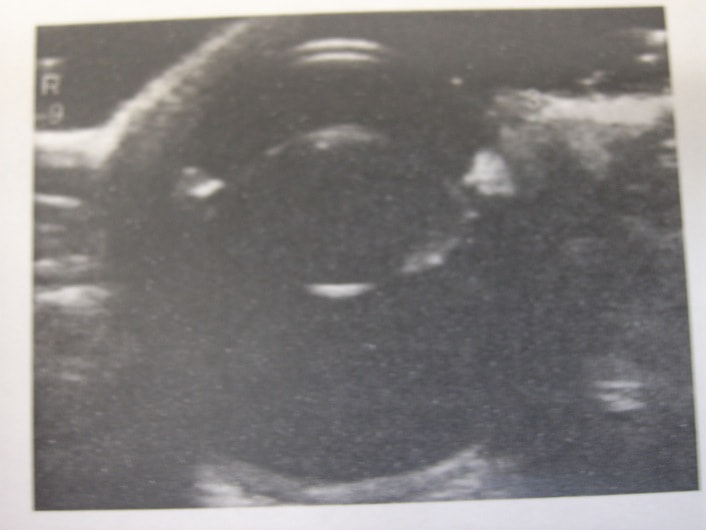

エコー検査:水晶体の厚み、硝子体内の状態、網膜剥離の有無などを観察することができます。

① 診察:全身評価・眼科検査(涙液検査・細隙灯検査・眼圧検査・エコー検査など)